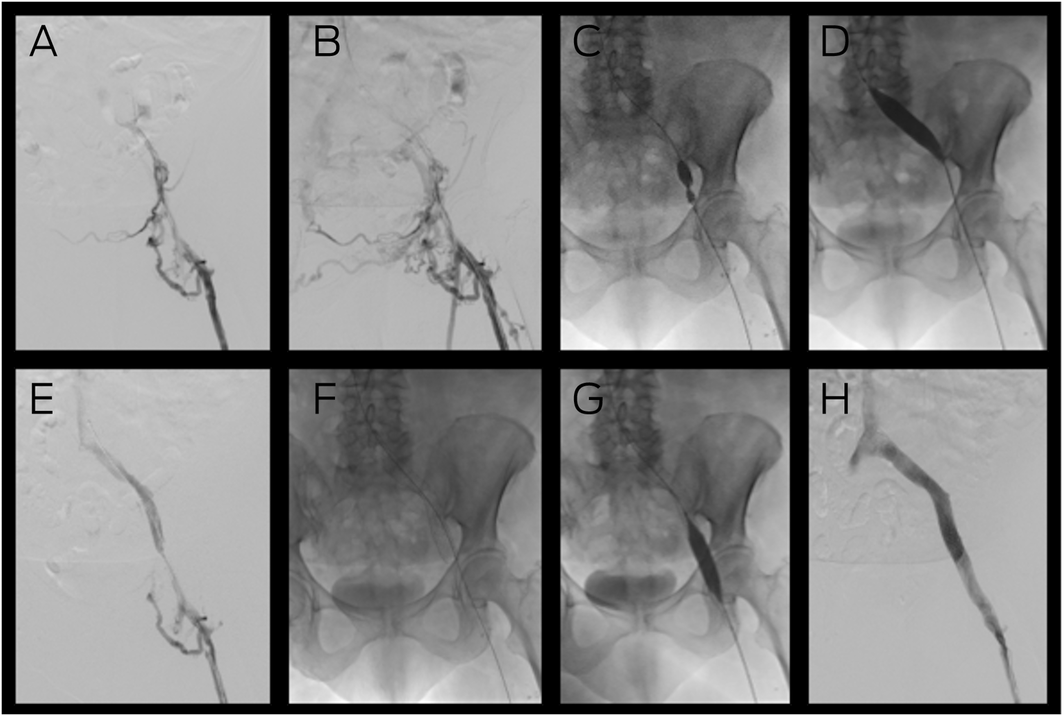

Box 2 – Venous stent placement for the management of post‐thrombotic syndrome due to occluded left iliac veins*

* (A) Venography demonstrating inflow from the femoral vein but no flow into the iliac veins, with (B) considerable collaterals in the pelvis. Placement of a guide wire across the lesion enabled venoplasty of the external and common iliac veins with considerable narrowing of the balloon by scar tissue (C) which was overcome by a high pressure (20 Atm) Kevlar 16 mm balloon (D). Subsequent venography (E) demonstrated recanalisation of the iliac vein that enabled placement of a 16 mm nitinol venous stent (F) from the inferior vena cava (IVC) to the common femoral vein. Following completion venoplasty (G), completion venography (H) demonstrated restoration of normal flow from the leg to the IVC.